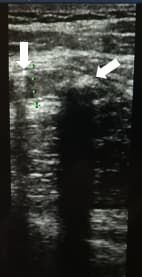

Аппендикс считается расширенным, если под действием компрессии его наружный переднезадний размер, измеренный при поперечном сканировании, более 6 мм (см. рис. 3).

Рисунок 3. Определение диаметра аппендикса.